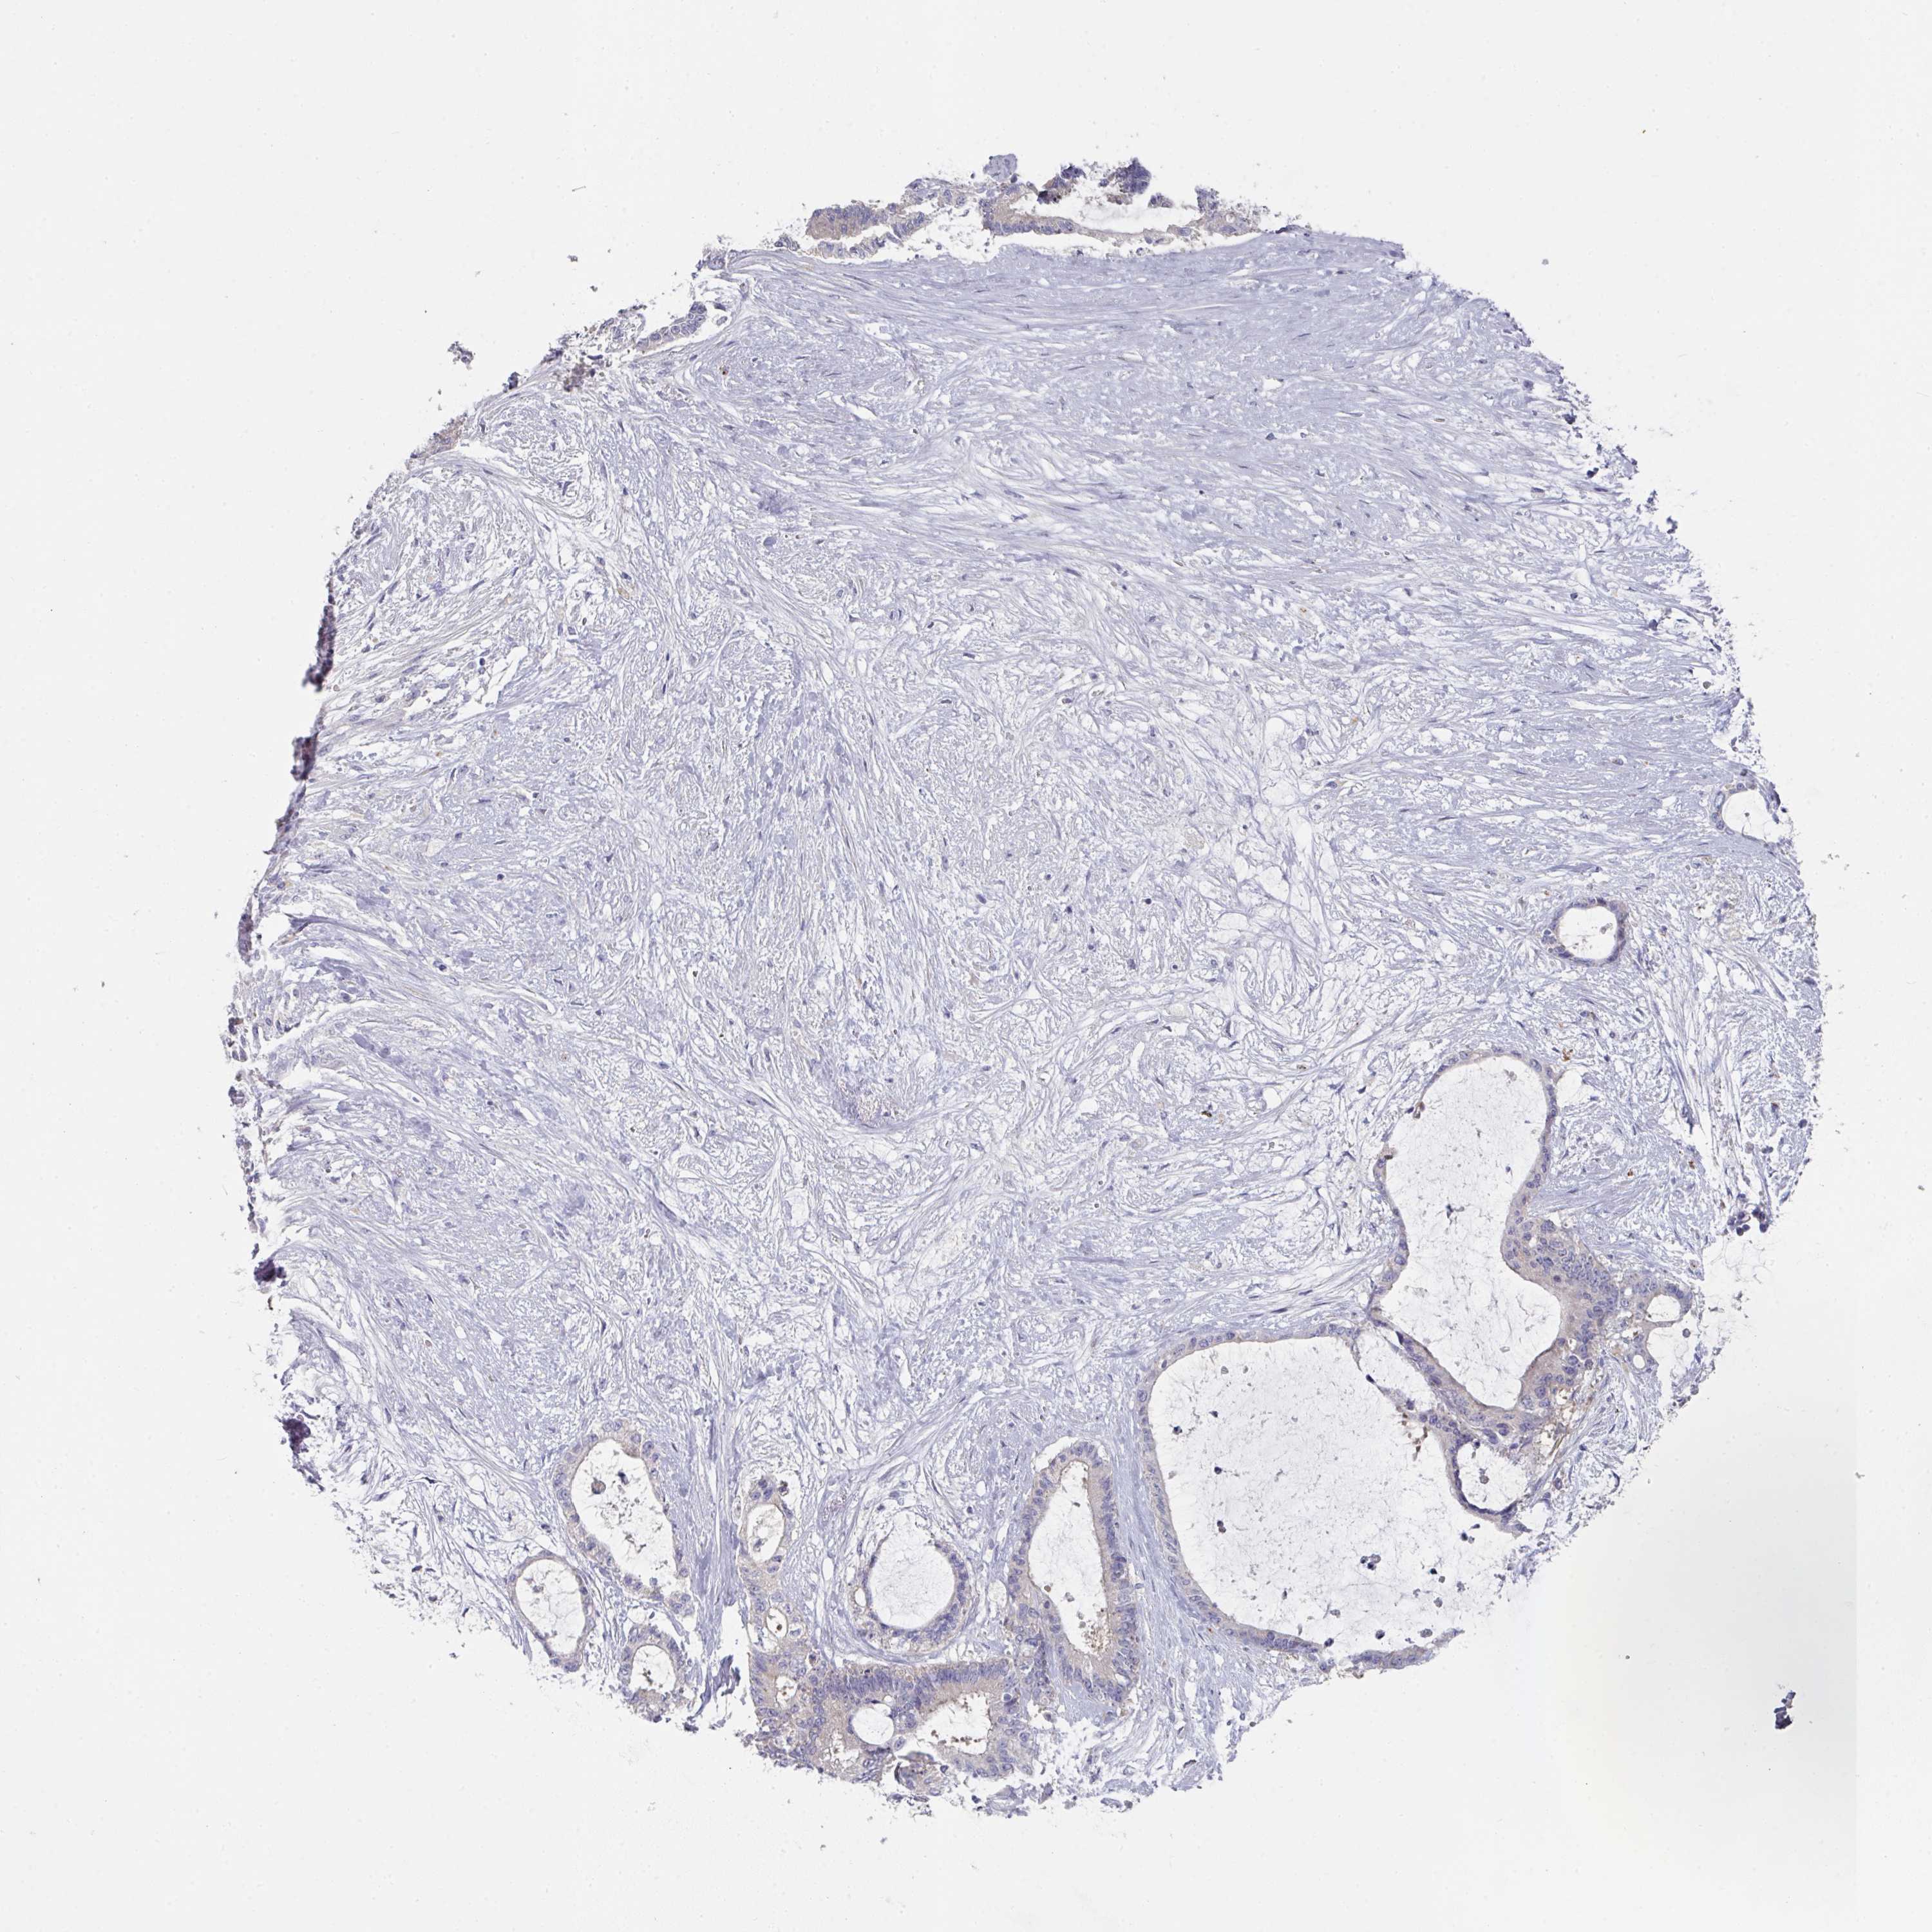

LIVER CANCER - Protein expressioni

A mouse-over function shows sample information and annotation data. Click on an image to view it in a full screen mode. Samples can be filtered based on level of antibody staining by selecting one or several of the following categories: high, medium, low and not detected. The assay and annotation is described here.

Note that samples used for immunohistochemistry by the Human Protein Atlas do not correspond to samples in the TCGA dataset.

Antibody stainingi

Antibody staining in the annotated cell types in the current human tissue is reported as not detected, low, medium, or high, based on conventional immunohistochemistry profiling in selected tissues. This score is based on the combination of the staining intensity and fraction of stained cells.

Each image is clickable and will lead to virtual microscopy that enables deeper exploration of all samples and also displays staining intensity scores, fraction scores and subcellular localization as well as patient and tissue information for each sample.

Antibody HPA050283

Antibody HPA054158

Staining

High

Medium

Low

Not detected

Intensity

Strong

Moderate

Weak

Negative

Quantity

>75%

75%-25%

<25%

None

Location

Nuclear

Cytoplasmic/membranous

Cytoplasmic/membranous,nuclear

Cholangiocarcinoma

Carcinoma, Hepatocellular, NOS